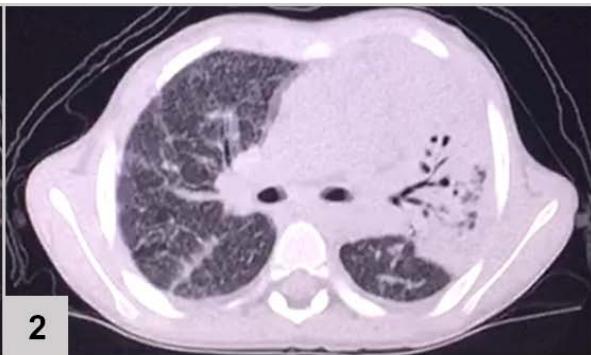

Lungbiopsy (FIGURE 2)

Figura 2: Lung biopsy (200x magnification). (1) Pulmonary tissue in hematoxylin and eosin showing granulomatous reaction with epithelioid histiocytes and multinucleated giant cells. (2) Pulmonary tissue in Grocott's stainrevealing fragments of broad, wavy and short hyphae, matching Zygomycosis by mucorales, longitudinal and cross-sectioned With the fungal lung infection diagnosis (zygomycosis), without previously response to Fluconazole, Amphotericin B was administered. The fever disappeared and there was no need for supplemental oxygen, the patient was discharged from the hospital with mild tachypnea.

The identification of the etiologic agent was possible through microscopy (FIGURE 2) that showed granulomatous tissue, and, through Grocott staining, fragments of hyphae compatible with Mucorales fungi. Histopathological examination represents the most reliable method for diagnosing pulmonary zygomycosis. Direct histomorphological visualization allows differentiation between Zygomycetes (short, tortuous broad hyphae of variable caliber with random branching at right angles) and Aspergillus fungi, and is extremely important because, clinically, lung infections caused by these fungi are indistinguishable[^7].